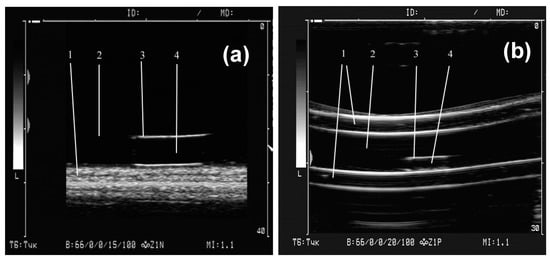

Figure 5 shows an example of a single ultrasound image frame when scanning a gel sample positioned at the bottom of a cuvette (a) and inside a model vessel (b) (Figure 2). The images very clearly show the boundaries of the gel samples lining at the bottom of the cuvette and the walls of the tube with water. It is also seen that the highest echogenicity of the gels (i.e., the largest amplitude of the reflected ultrasonic vibrations, and, accordingly, the brightness of the image) corresponds not to the sample body, but to the interface between the gel surface and the water. In experiments with the first batch of gels, the visualization was performed with an ultrasound device amplification of 15 dB. Four samples were tested for each concentration of MNPs in the gel. The average value of the maximum brightness of the water in the cuvette in all tests of the gels was 34.1 ± 0.2 (n = 16).

Figure 5.

Examples of ferrogels samples visualization at the bottom of water cuvette (a) and inside a silicone tube filled with water (b). The distance from sensor to objects is about 20 mm. 1—soft pad (a) and wall of silicone tube (b); 2—water in cuvette (a) and in tube (b); 3—upper boundary of gel/water; 4—gel body.